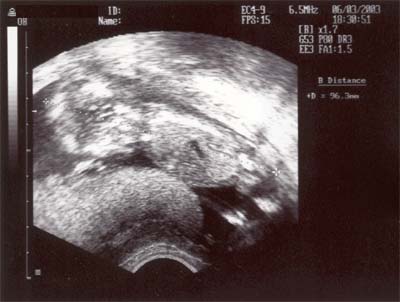

Das Ultraschallbild von mir.

Ich bin jetzt schon 96,3mm gross - staun -